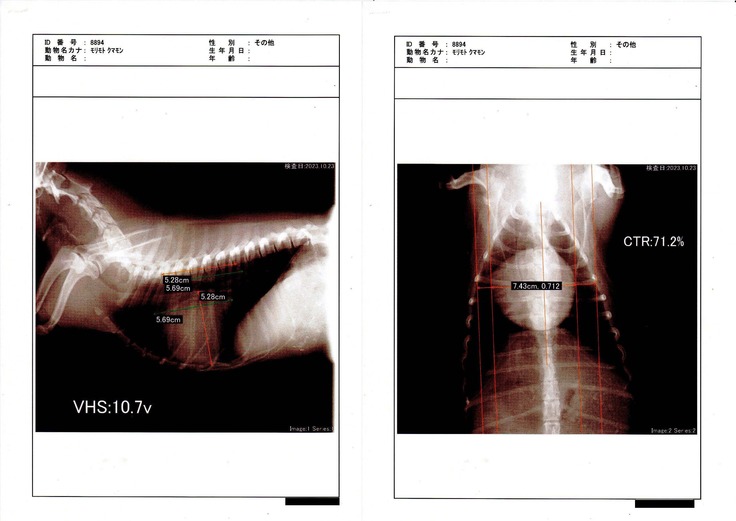

【心臓レントゲン写真】

レントゲン写真の数値は心臓の大きさを測ったものです。

小さくなっているような気もしますが、横に広がった感じもします。